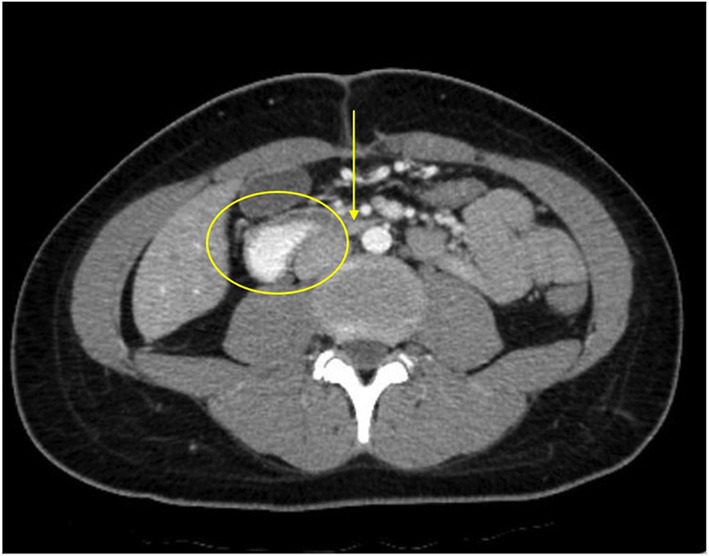

At presentation, the patient reported a rapid weight loss of more than 9 Kg. She denied constipation, diarrhea, or intentional vomiting or weight loss. She was noted to have a normal body mass index (BMI) of 23.46 Kg/m2, despite her weight loss. Physical examination was remarkable for diffuse abdominal tenderness and fullness to palpation, worst in the epigastrium. ß-hCG was again negative and urine toxicology screen was positive for tetrahydrocannabinol (THC). Abdominal x-ray was unremarkable. CT scan with contrast of the abdomen and pelvis revealed moderate gastric and proximal duodenal distention, with tapering of the duodenal lumen at the level of the SMA. The aortomesenteric (AOM) angle was 10 degrees and AOM distance was 6 mm. Taken together, these findings were suggestive of SMAS (Figures 2, 3) (ref. 3). There was no evidence of biliary or pancreatic pathology, adenopathy, or malignancy. A nasogastric tube was inserted for gastric and duodenal decompression and a nasojejunal (NJ) tube was placed to bypass the obstruction and provide nutrition and hydration.

The differential diagnosis for our patient’s acute illness, in addition to SMA syndrome, included: small bowel obstruction, gastric or duodenal dysmotility (e.g., gastroparesis, ileus), collagen vascular disease (e.g., scleroderma), chronic idiopathic pseudo-obstruction, and peptic ulcer disease. The decreased AOM angle of less than 22 to 28 degrees and AOM distance between 2 and 8 mm in association with the patient’s symptoms, however, were diagnostic of SMA syndrome (ref. 8–ref. 10).